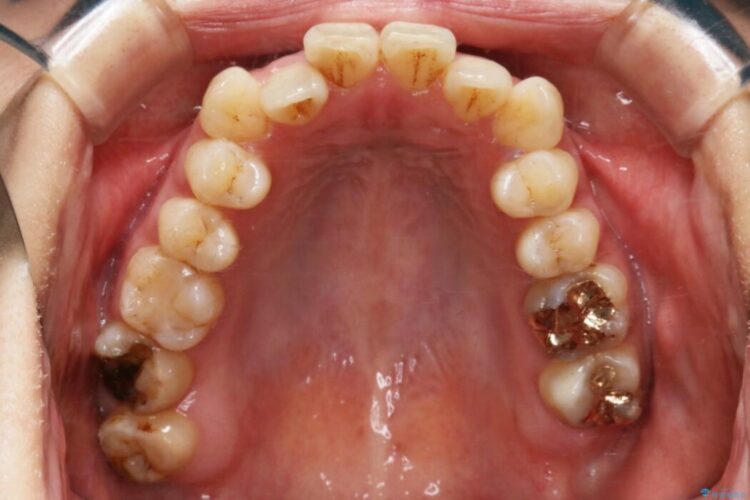

開咬により上下の噛み合わせが悪く、歯列の凸凹も合わせて治療したいとのことで来院されました。

なるべく非抜歯にて治療をするためインビザライン(マウスピース)とマイクロインプラントを併用した治療を行いました。